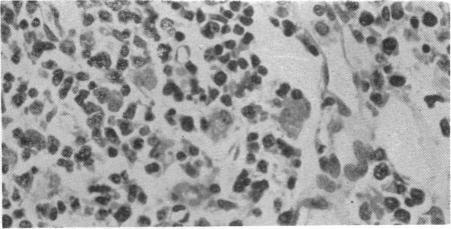

Development of hirsutism after puberty.

Br Med J. 1958 Dec 27;2(5112):1554-7. doi: 10.1136/bmj.2.5112.1554.